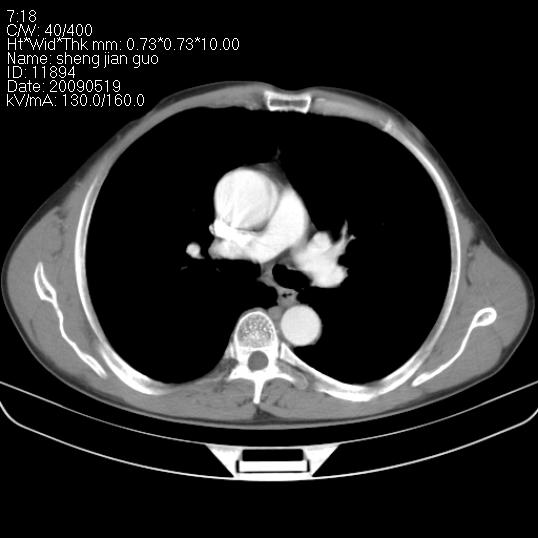

以下是引用zjzjr在2009-5-19 17:25:00的发言:[br]支持楼主考虑,另左肺下叶阻塞性炎症。

以下是引用zhao_bin2008在2009-5-19 17:48:00的发言:[br]支持左肺下叶周围型肺癌并阻塞性肺炎。

以下是引用zsl6918在2009-5-20 7:10:00的发言:[br]左侧中心型肺癌!